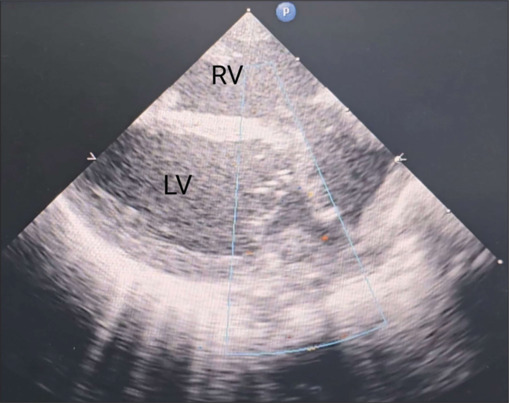

Cardiac rhabdomyomas are the most common primary cardiac tumors observed in neonates and children, which have been frequently associated with the tuberous sclerosis complex. These benign tumors usually have a natural history of regression but can sometimes cause significant clinical issues by obstructing blood flow and arrhythmias. We present an unusual case of a neonate who presented with a large cardiac rhabdomyoma with obstruction to the right ventricular inflow and outflow. The tumor necessitated an urgent surgery, which proved to be technically challenging.